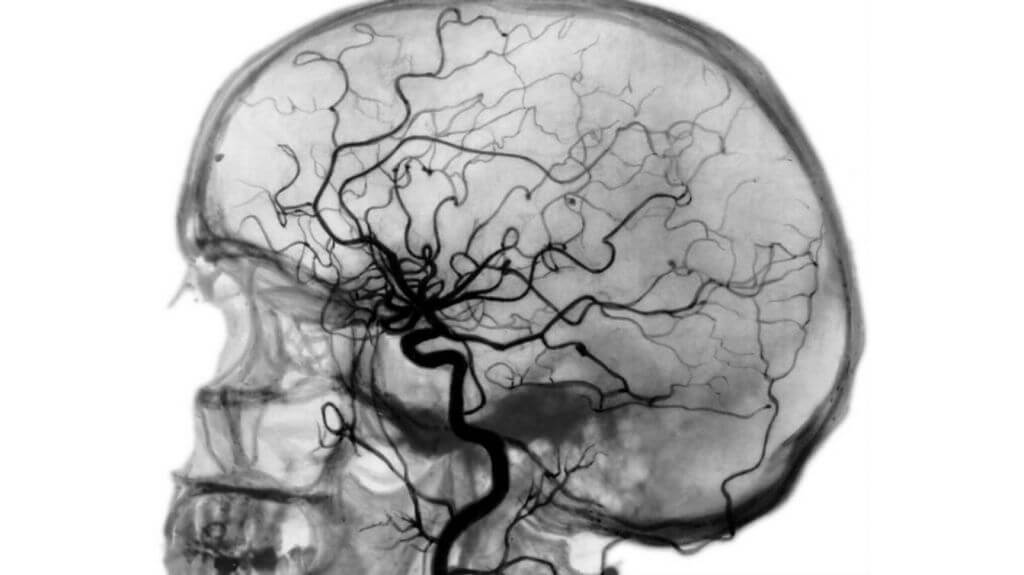

Ангиография

Ангиография исследует кровеносные сосуды изнутри, «просвечивая» их рентгеном. Врач вводит в кровеносную систему человека рентгеноконтрастное вещество. По тому, как оно распределяется по сосудам, доктор определяет разные нарушения: сужение, расширение или полную остановку тока крови в изучаемой области. Исследование проводится при подозрении на состояния, угрожающие жизни: инсульт, опухоль, атеросклероз или аневризму.

Ангиография – процедура достаточно серьезная и инвазивная. Она имеет противопоказания (инфекции, воспаления, почечная и печеночная недостаточность, беременность) и, в отличие от других типов сканирования, требует подготовки. Пациент заранее сдает флюорографию, лабораторные анализы и приходит на исследование натощак.